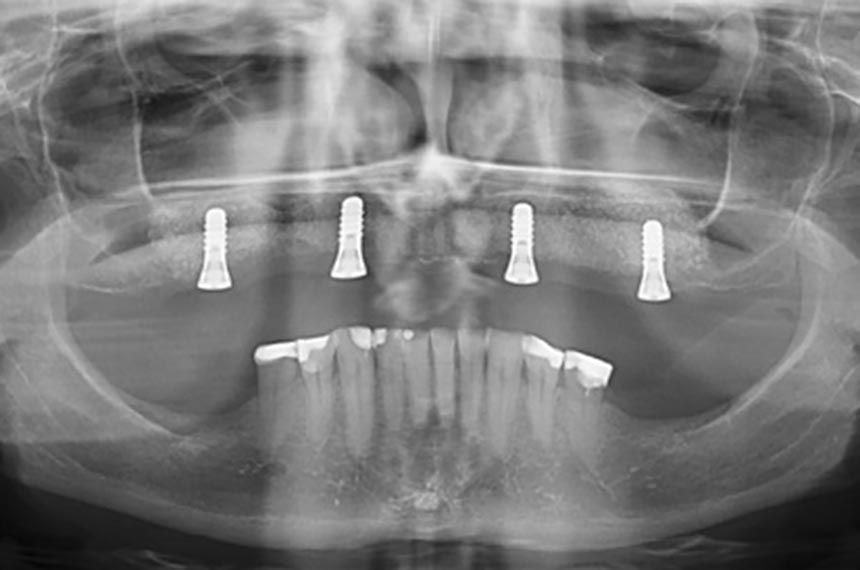

The teeth and roots in the upper jaw were extracted in toto, and the existing denture was relined with tissue conditioner. After a sufficient healing time, the oral surgeon performed the augmentation procedures under local anesthesia. A ridge incision in the region UR7 to UL7 with two distal reliefs in the vestibule was performed. The mucoperiosteal flap was carefully raised, and bone chips were harvested with a bone scraper. The maxillary sinuses on both sides were opened with lateral windows, and the augmentation was performed with the bone graft mixed with bone xenograft in the ratio 1:1. In the canine regions the buccal cortical bone was perforated, and the bone graft was applied laterally and covered with a collagen membrane. After perforation of the periosteum the margins of the flap were fixed with simple interrupted sutures using Seralon® (5-0). The post-operative medication included ibuprofen 600mg and Aziclav 2x1gram/day and disinfectant mouthwash. After a sufficient healing time the implants (all Straumann, SP, 4.1mm, RN, SLAactive, TiZr, 10mm) were placed in the regions UR6, UR3, UL3, UL6 with good primary stability. A smaller bony defect in the UR3 region was covered with a mixture of bone chips and bone xenograft. The flap was sutured to allow for transgingival healing of the implants with adequate healing caps. Post-operative medication included ibuprofen 600mg, Aziclav 2x1gram/day and disinfectant mouthwash. After eight weeks healing time the implants showed high ISQ-values: UR6 (75), UR3 (77), UL3 (84), UL6 (86) and the oral surgeon referred the patient back to the prosthodontist for the reconstructive phase (Figs. 1-2).